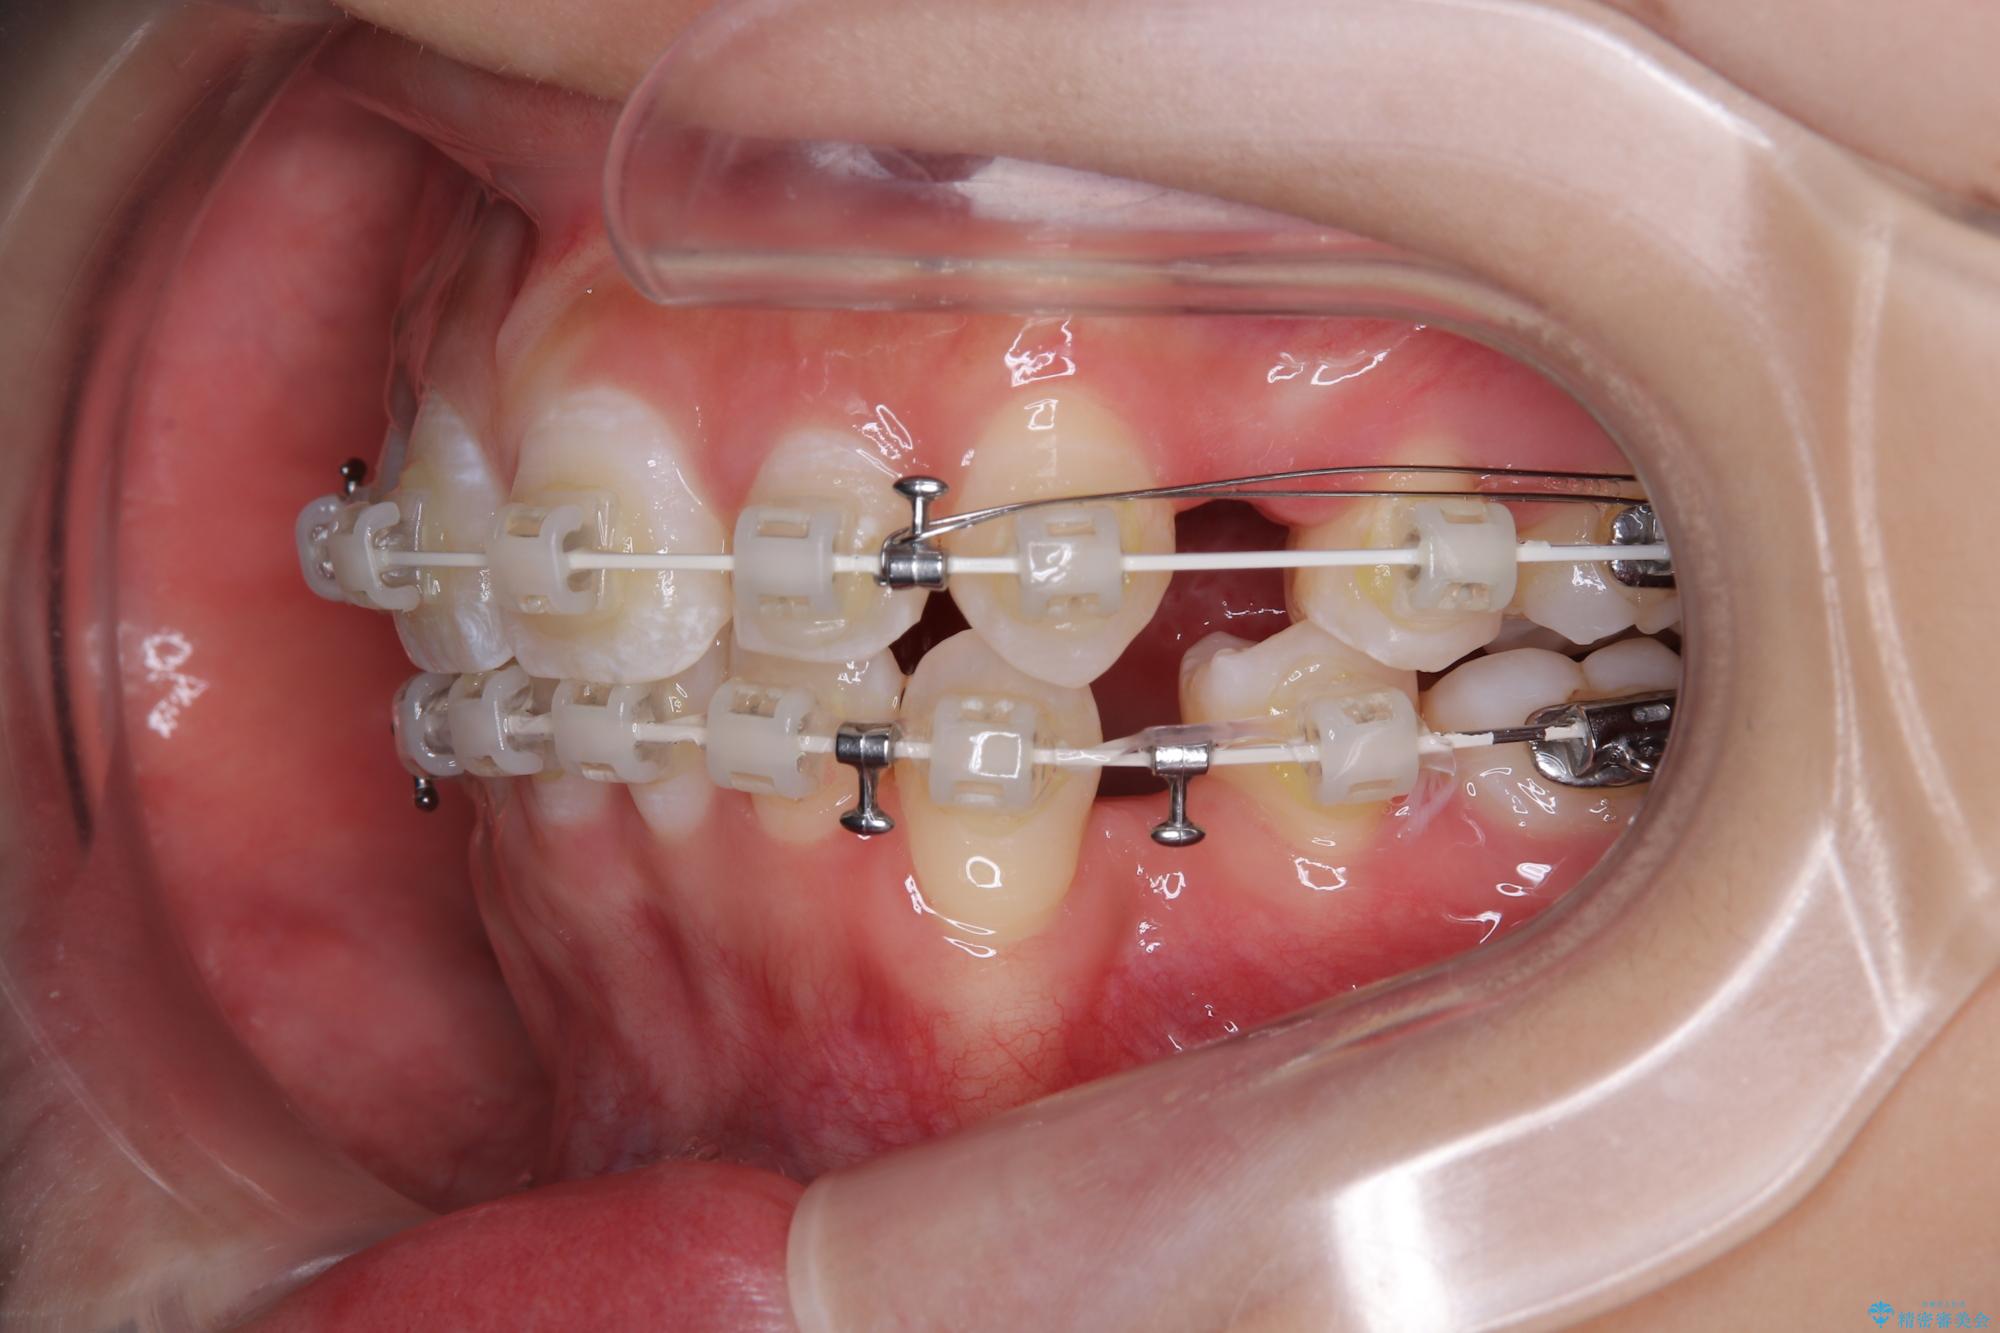

- 矯正装置

- 審美装置

- 2年

- 10-30回